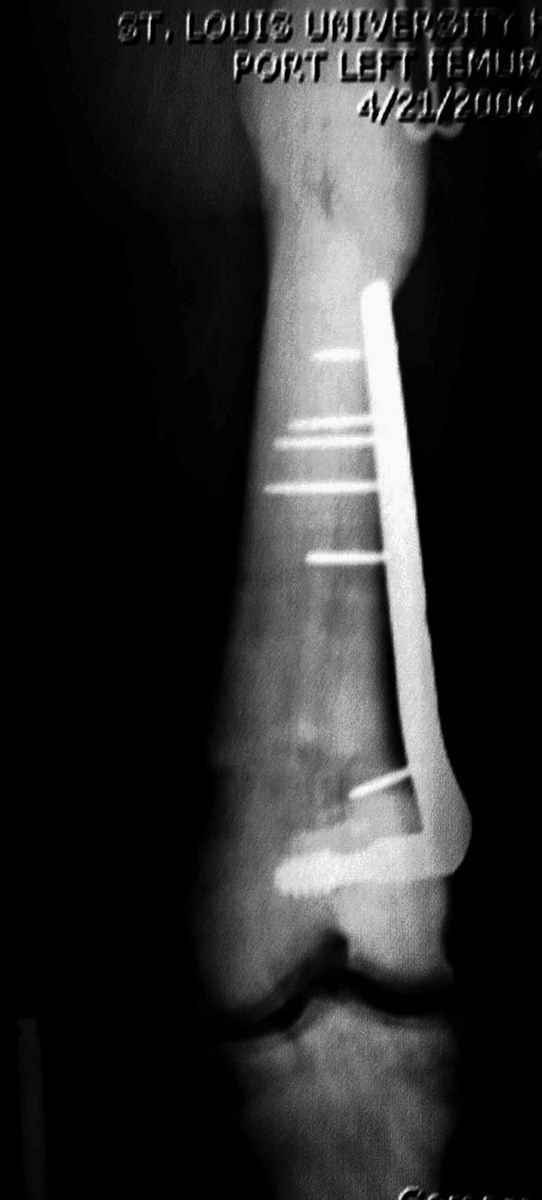

Здесь у меня дополнительные снимки с большим разрешением и в разных режимах, а то те дигитал снимки совсем очень блеклые, может, эти изображени изменят выбор тактики

Любой стандартный штифт для проксимального отдела бедра пройдет. TGN действительно из всех самый короткий, и поэтому предпочтительнее.

Не вызывает ли подозрение, что отсутствует медуллярный канал, как просверлить канал?